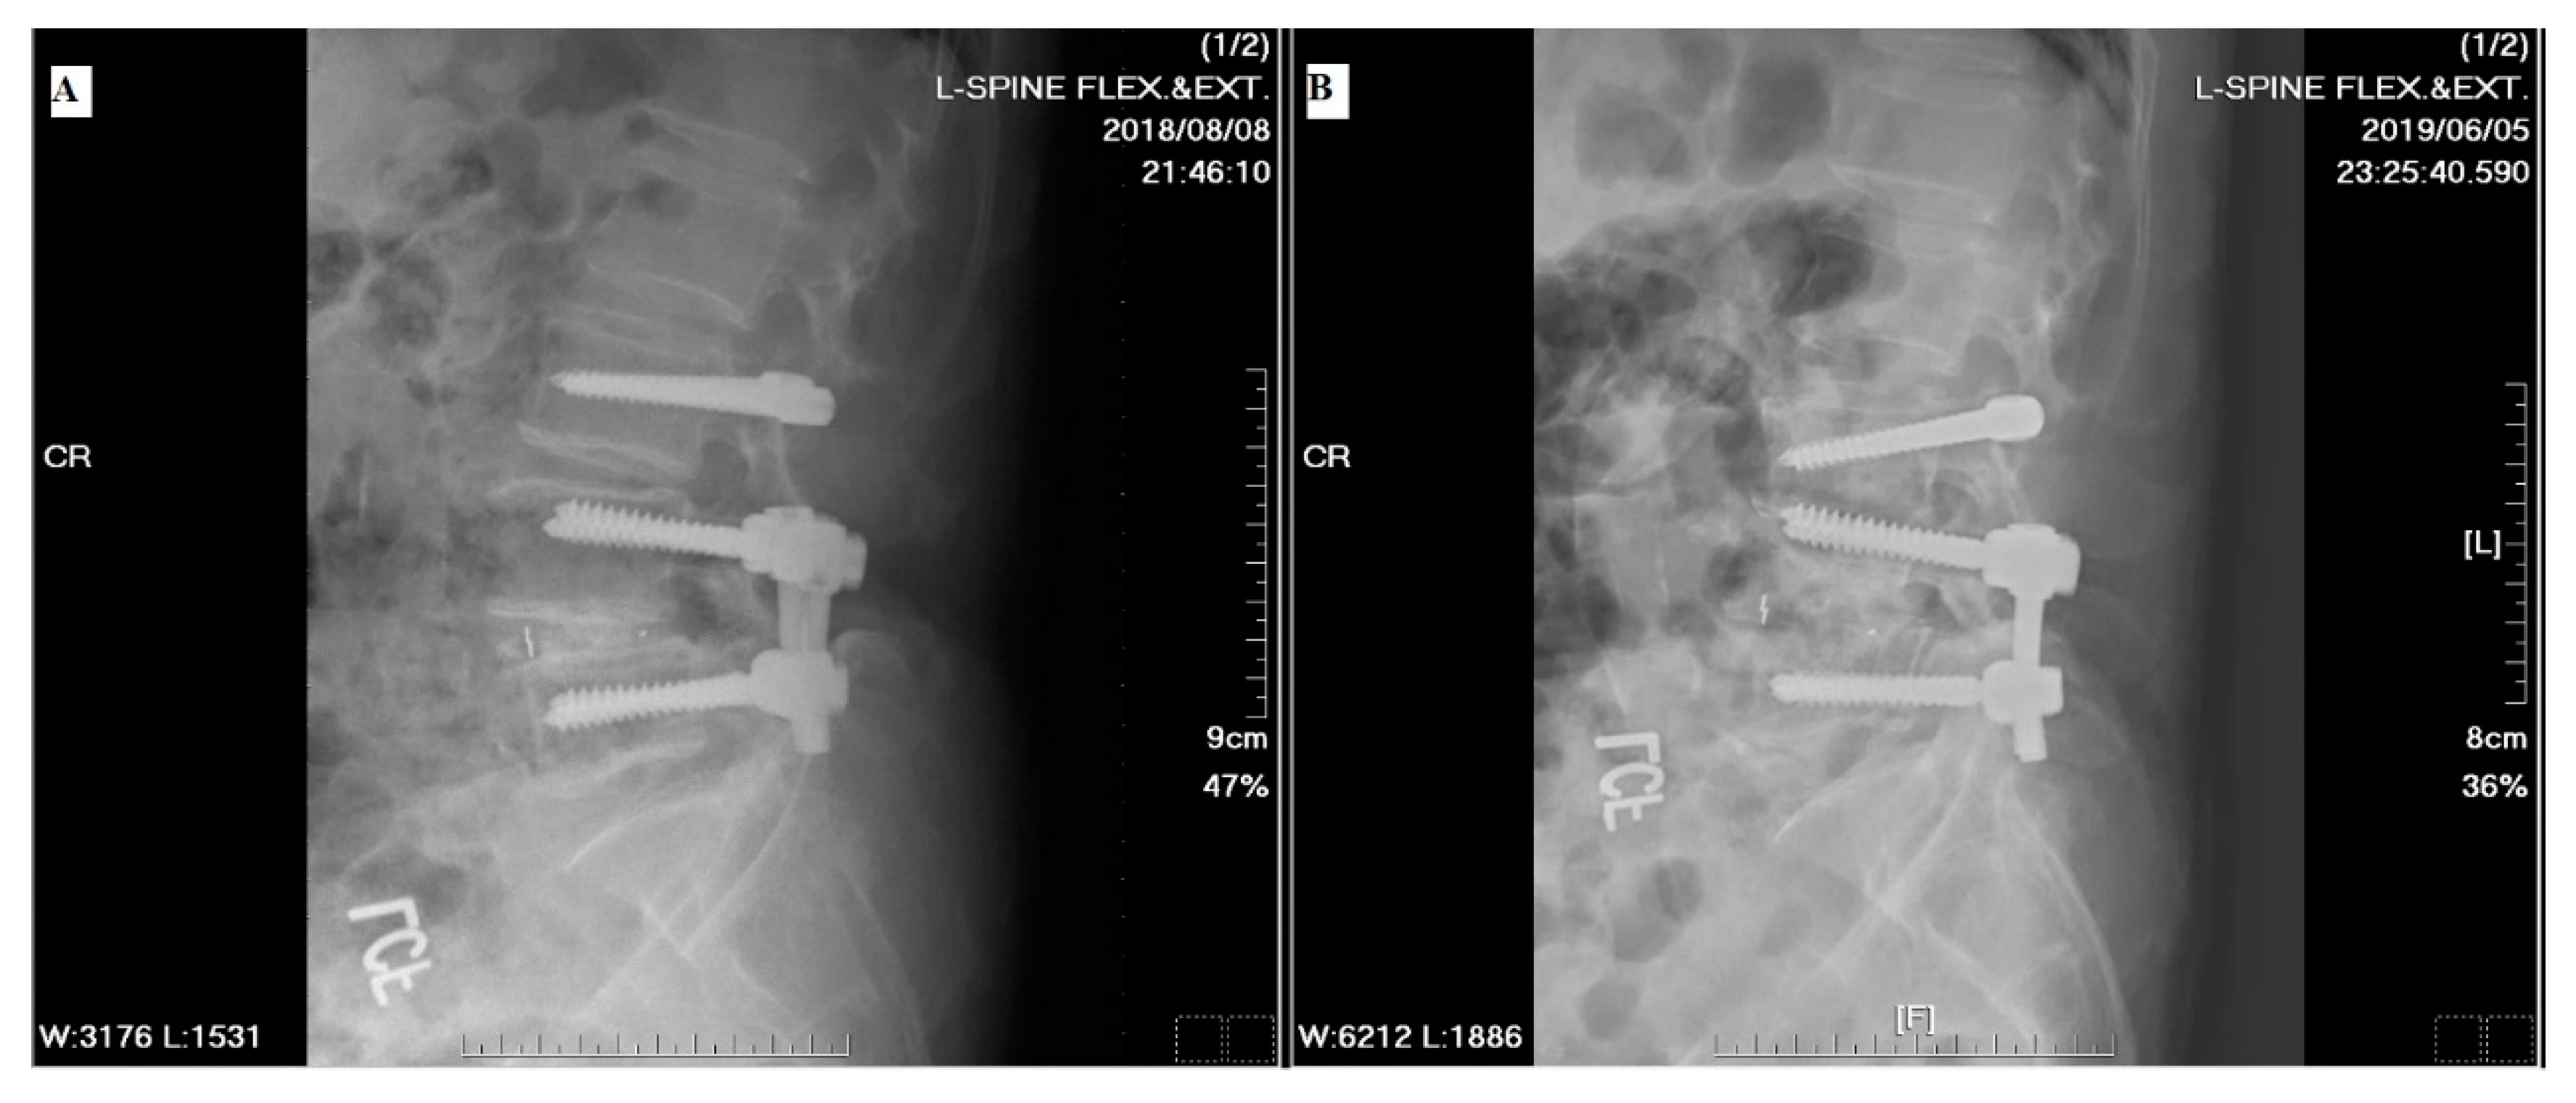

2.3. Surgical Techniques